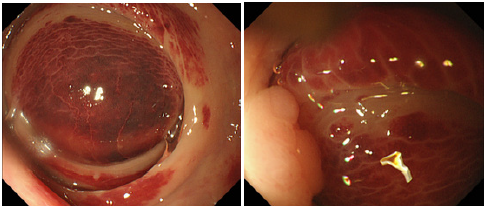

Figure 3:

(a): Sigmoidoscopy showed a large dark-red mass in the rectum above the peritoneal reflection.

(b): On the anal side, sigmoidoscopy showed a polyp (white arrows) which was interrupted to perform endoscopic

mucosal resection in the previous time. Purpura in the polyp and the mucosa around it was improved.